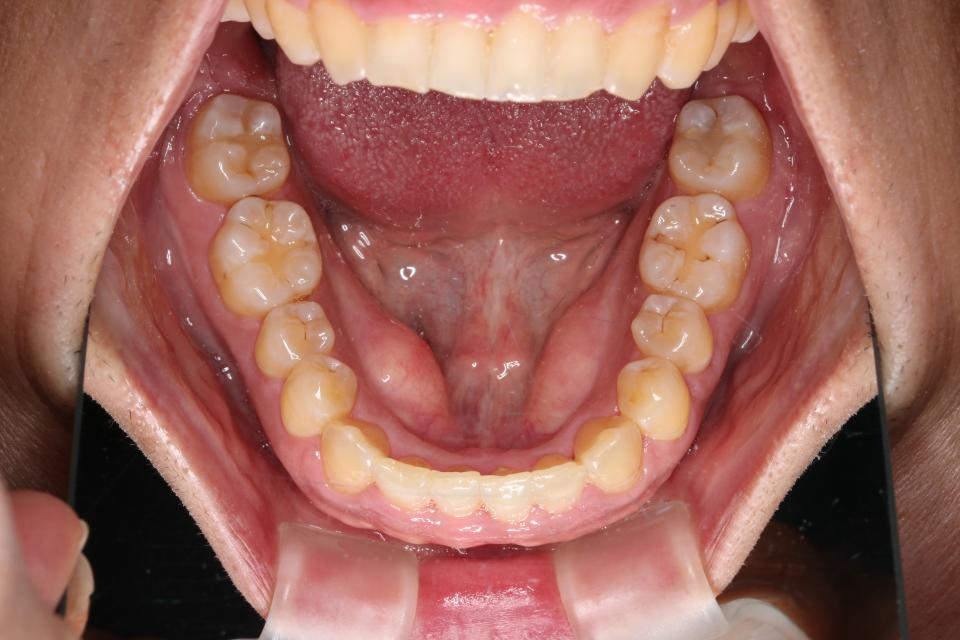

叢生(がたがた)のマウスピース型矯正治療例

矯正治療後

30代男性です。

歯の凸凹が気になると来院されました。

目立たない装置・取り外し可能なマウスピースタイプでの矯正治療を

希望されてましたのでマウスピース型矯正装置(インビザライン)で矯正治療を行いました。

親知らずを3本抜歯して、歯のやすりがけ(IPR)を行っています。

| 矯正治療期間 | 2年8か月 |

| 抜歯の有無 | 3本親知らず抜歯 |

| 治療費 | 1005000円 |